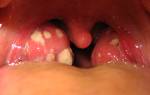

Конъюнктивит

Появление воспалительного процесса в конъюнктиве может негативно сказаться на зрении и часто становится причиной обращения к офтальмологу. Наиболее распространенные факторы, вызывающие конъюнктивит, включают переохлаждение, простудные заболевания и аллергические реакции.

Инфекционные агенты могут вызвать заболевание, проникая в слизистую оболочку через грязные руки, полотенца или игрушки, особенно после повреждения ткани (например, щепкой или ресничкой). Воспаление обычно затрагивает один глаз, но при отсутствии лечения может распространиться и на второй.

У детей конъюнктивит протекает тяжелее, чем у взрослых. Заболевание сопровождается рядом местных симптомов:

- рези и ощущение песка в глазах;

- отечность век;

- жжение;

- повышенная чувствительность к свету;

- склеивание век по утрам;

- желтые корочки, свидетельствующие о выделениях;

- покраснение конъюнктивы.

Кроме того, общее состояние ребенка может ухудшаться. Он становится вялым, капризным и плаксивым, у него может снизиться аппетит и возникнуть проблемы со сном. Дети старшего возраста могут жаловаться на ухудшение зрения и трудности с четким восприятием предметов из-за размытости их очертаний.

Появление желтого отделяемого указывает на гнойное воспаление. Если наблюдается сильное слезотечение без гнойных выделений, это может свидетельствовать о вирусной или аллергической природе заболевания. В таких случаях избыточная жидкость выводится через носовые проходы.